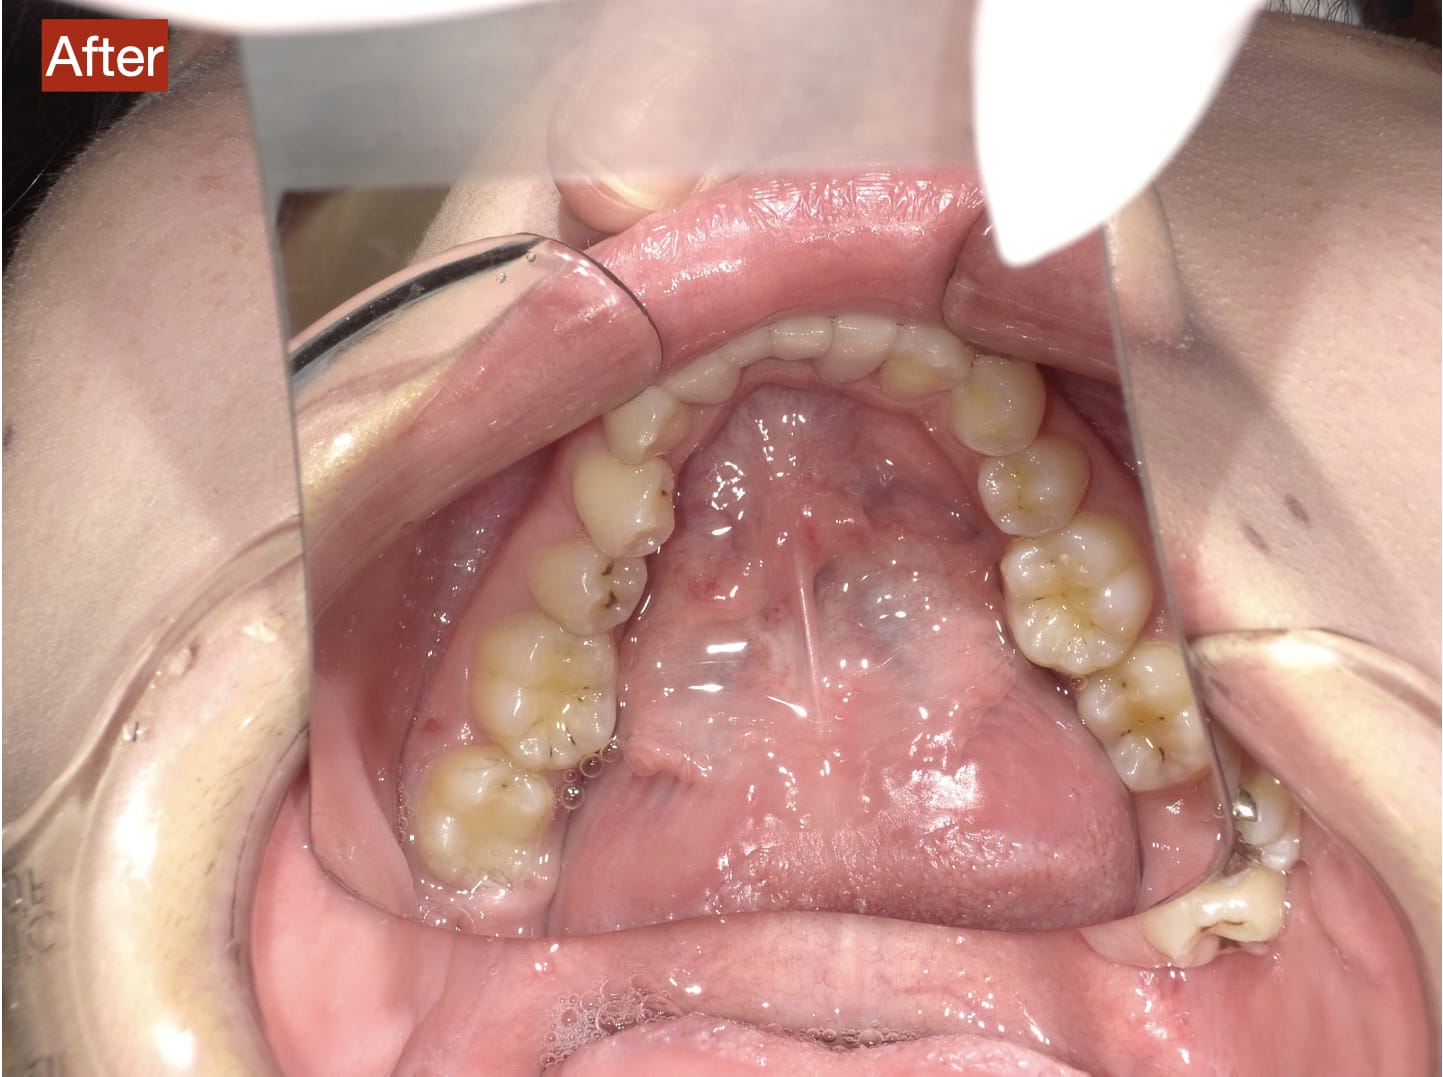

Case029

セラミック矯正の患者様です。

・上下の歯の入れ違い

・正中の歪みと隙間

を主訴にご来院くださいました。

この患者様は若年性歯周炎にかかってしまったため、一生懸命に歯を磨き、口の中は綺麗なのにも関わらず歯茎が下がってしまい、隙間が出来てしまっています。

これは矯正治療で歯の並び方を変えても絶対に無くなりません。

そのため、患者様の主訴を叶えるためにセラミック矯正で治療計画を練りました。

前のクリニックでは「上下一本ずつ抜糸してブリッジで矯正する」という計画だったようですが、

・患者様が非抜歯を希望されていること

・歯を抜かなくても綺麗に並べられそうだったこと

を理由に、当院では上は抜かずにセラミック。下は形態修正だけで対応しました。

この方針変更だけでもお値段も安く、また侵襲(ダメージ)を少なくすることができました。

治療の結果、最低限の侵襲で、見違えるほど綺麗な口元に治療することができ、患者様もとても喜んでくださいました。

主訴とご希望によって、ワイヤー矯正、マウスピース矯正、セラミック矯正のどの矯正が適しているかは異なります。

当院では上記全ての治療法に対応することができるので、主訴とご希望に沿った方法で治療することが可能です。

カウンセリングにてご希望をお伺いした後、一つ一つの治療の違い、当院のおすすめをご紹介いたしますので、ご希望の治療方法をお選びいただけます。

歯並びなどお口元にお悩みのある方、より綺麗な口元になりたい方はぜひ一度ご相談ください。

【主訴】

・上下で入れ違っている前から2本目の歯のすれ違いを治したい。

・清潔感のある白さで明るい綺麗な口元にしたい

・歯の隙間を無くしたい

【ご要望、ご状況】

・歯を抜かずに治したい

・前医では上下1本ずつ抜歯をして、ブリッジで上3本、下3本の計6本を治すことを提案された。

【今回の治療法】

・右上の犬歯から左の前歯までの計4本をジルコニアセラミックで治療

・色は自分の歯よりやや白いくらいでホワイトニングをしてもしなくても大丈夫なくらいの白さ

・歯は抜かない

・右下の歯は形態修正だけで対応

・歯茎のラインを歯肉整形術で整える